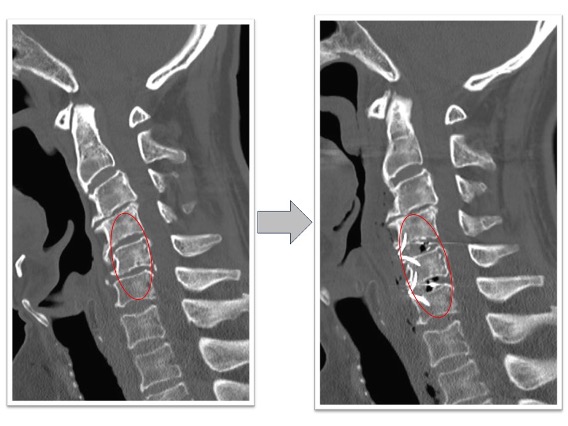

経皮的椎体形成術実例(*患者様の許可を得て掲載しています)

胸椎圧迫骨折

胸椎圧迫骨折後、遷延する腰痛と骨癒合不良を認めていた椎体に対してBKPを実施しています。治療後レントゲン画像では椎体内に注入された骨セメントと椎体高が改善していることが確認できます。腰痛改善し術翌日に退院となっています。